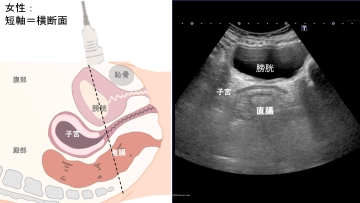

現場でエコーを活用するには、解剖学と画像の読み方の理解が欠かせません。実演前には、男女別や描出断面(短軸・長軸)ごとの解剖学的特徴と画像の見え方を、イラストと実際のエコー画像を交えて丁寧に説明します。もちろん、エコー初学者向けに輝度や超音波の特徴、活用できる看護場面、アセスメント後の看護ケアの選択まで網羅します。